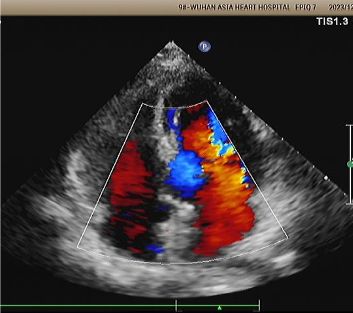

Implante: 2424 MemoSorb®Oclusor PFO biodegradável implantado sob orientação eco e DSA.

Dias 1 a 9 meses:

Nenhum desvio residual observado.

Redução gradual da ecogenicidade do dispositivo.